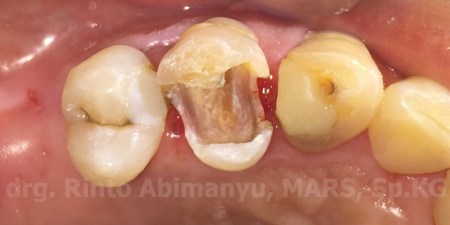

Kondisi klinis setelah selesai preparasi saluran akar

Kavitas terlihat bersih dengan jalan masuk yang lurus ke arah saluran akar

Untuk basis menggunakan SDR (Dentsply) kemudian dilanjutkan menggunakan komposit Z 350 XT (3M) untuk bagian atasnya. Setelah dicek oklusi, pemolesan menggunakan Diacomp Twist (Eve).

Hasil restorasi setelah pemolesan…

Hasil akhir restorasi